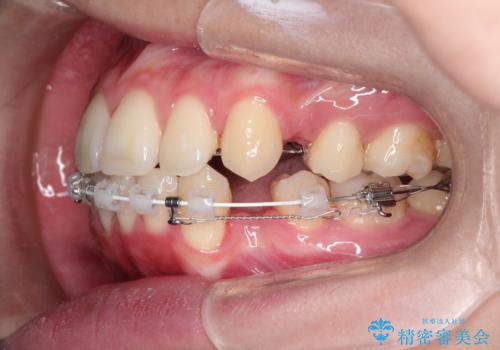

口元が出てるの気になる ハーフリンガルによる抜歯矯正での横顔改善

- 前歯が出ているため口が閉じにくく、横顔が気になるとのことで来院された患者様です。。

上下の前歯が前方に傾斜しており、口唇の突出感がありました。

上下左右の前から4番目の歯を抜歯して、上下の前歯を後方に移動させる計画としました。

抜歯矯正により、前歯をしっかり下げることで口元がすっきりしました。